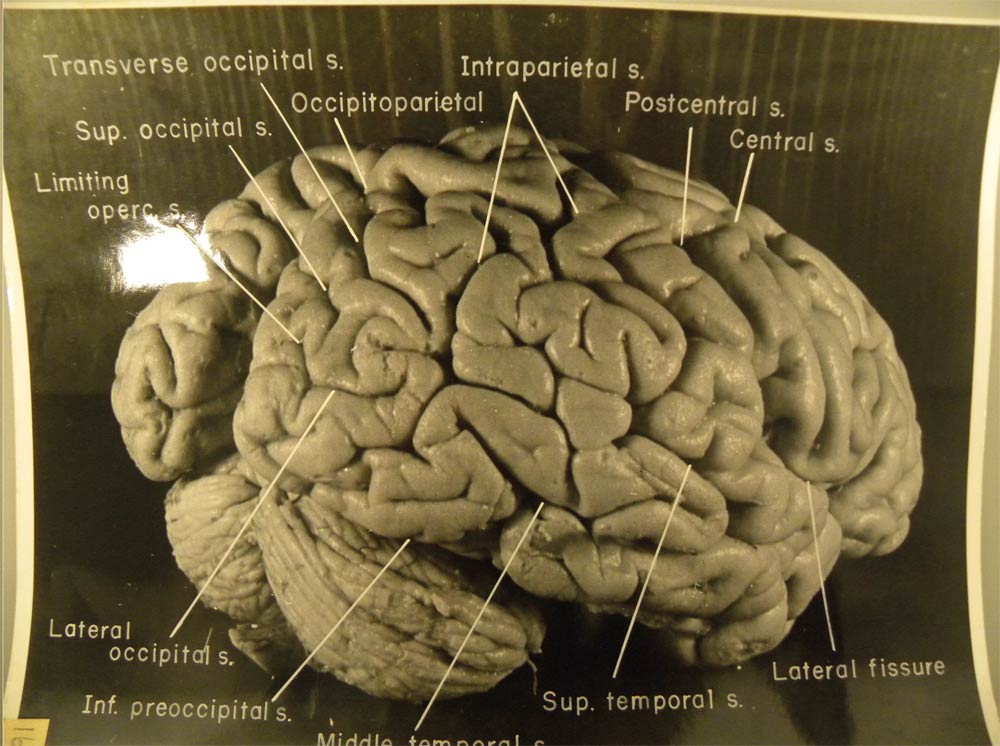

Https www alamy com a specimen of nobel physicist albert einsteins brain is seen in a glass slide at an exhibition at the wellcome collection in london march 27 2012 weve pickled it dessicated it drilled it mummified it chopped it and sliced it over centuries yet as the most complex entity in the known universe the human brain remains a mysterious fascination with samples of albert einsteins preserved brain on slides and specimens from other famous and infamous heads such as the english mathematician charles babbage and notorious mass murderer william burke an exhibition opening in london this week image377121679 html (Dateityp jpg)

Einsteins Brain High Resolution Stock Photography And Images Alamy